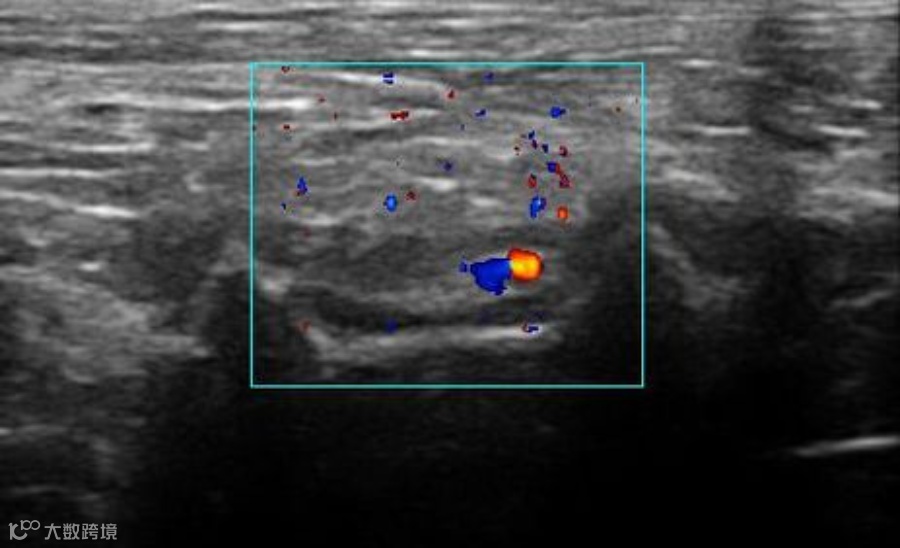

EchoSure是一种超声诊断系统,可以自动检测血流、血管直径和深度等关键的血管参数。这些数据对于评估动静脉瘘的成熟度和功能至关重要,可以帮助医生确定最佳的透析通路,并及时干预以提高手术成功率。

2019年3月,EchoSure 系统获得了美国 FDA 的批准。EchoSure 系统结合了 3D 超声成像和先进的深度学习算法,能够自动化地监测手术后的视觉和定量血流。

当与 EchoMark 标记物一起使用时,护士可以在没有超声培训的情况下,在透析诊所轻松监测患者,收集动静脉瘘的体积流量、直径和深度信息,以协助成熟度评估。